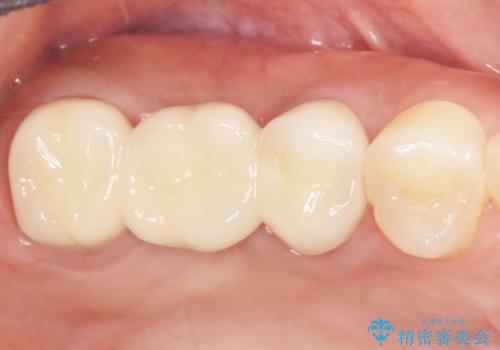

インプラントや入れ歯を使わずに奥歯でしっかり咬むことができるようになり、また見た目も自然だと大変喜んで頂けました。

クラウンの種類:メタルボンドクラウン エコノミー フルベイク